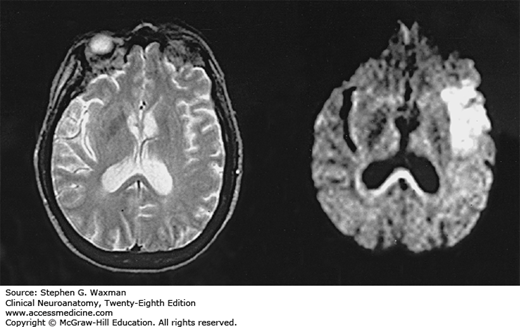

Cerebral infarct shown by diffusion-weighted imaging (DWI). On the left, a conventional MRI (T2-weighted image) 3 hours after stroke onset shows no lesions. On the right, DWI 3 hours after stroke onset shows extensive hyperintensity indicative of acute ischemic injury. (Reproduced, with permission, from Warach S, et al: Acute human stroke studied by whole brain echo planar diffusion weighted MRI. Ann Neurol 1995;37:231.)